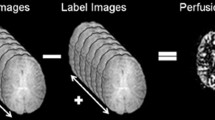

Arterial spin labelling (ASL) is a method of non-contrast-enhanced perfusion imaging that is generally based on the acquisition of two images which must be subtracted in order to obtain perfusion-weighted images. This is also the case for some flow territory mapping approaches that require the acquisition of two images for each artery of interest, thereby prolonging scan time and yielding largely redundant information. The aim of this study is to accelerate flow territory mapping using ASL by eliminating the acquisition of a control condition.

Using super-selective ASL, only one artery of interest is tagged, while the contralateral arteries are in a state similar to the control condition. By using an arithmetic combination of the label images of all territories, selective images of flow territories can be obtained without the need to acquire an additional control condition. This approach for obtaining artery-selective perfusion-weighted images without acquiring a control condition is presented in this study and is referred to as "self-controlled super-selective ASL".

In non-selective and super-selective ASL, images are obtained by subtracting the label from the control image. Through subtraction, the static tissue components are removed, while in blood, a difference signal remains. Using super-selective ASL, this calculation must be repeated for each artery.

In self-controlled ASL, no control condition is acquired, and the artery-selective images can be obtained using a combination of the two contralateral acquisitions, with subtraction of the duplicate acquisition of the artery of interest, as follows:

RICA and LICA indicate the label images of the right and left carotid artery, respectively, and BA indicates the basilar artery. A schematic of the RICA calculation is presented in Fig. 1. In the flow territories of contralateral arteries, the calculation leads to a negative signal. These voxels are set to zero.